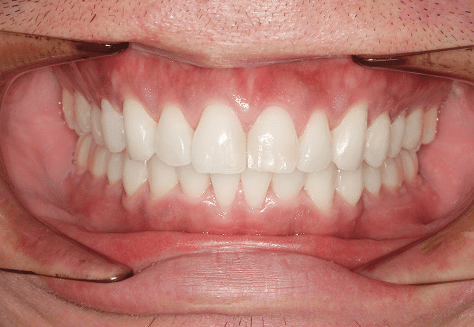

H.A

治療前

治療後

主訴

正中がずれているのが気になる。ちゃんと噛めていない。

診断

上下両側第二小臼歯先天欠如・上顎前突

年齢/性別

10代/女性

抜歯部位

必要に応じて乳歯抜歯

使用装置

6か月間エッジワイズにて下顎第一大臼歯の近心傾斜改善→上下インビザラインへ移行

保定装置

上下ビベラリテーナー

料金

初回資料採得・・・・・・・15,000円

診断料・・・・・・・・・・33,000円

動的治療終了時資料採得・・5,500円 -

基本料金

936,000円

診察料金

ワイヤー時:5,500円×4回

インビザライン時:1,100円×21回 -

治療期間

2年4カ月